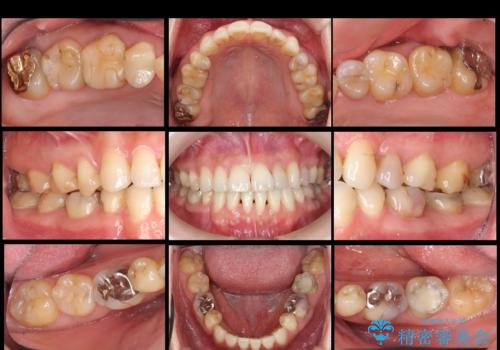

全体的な虫歯治療

治療症例の内容

- 他院で矯正治療終了後、健診をご希望されました。

神経の治療や詰め物のやり直しなど、全体的な治療を行っています。

左下6番、左上4番は失活していたため、根管治療を行っています。